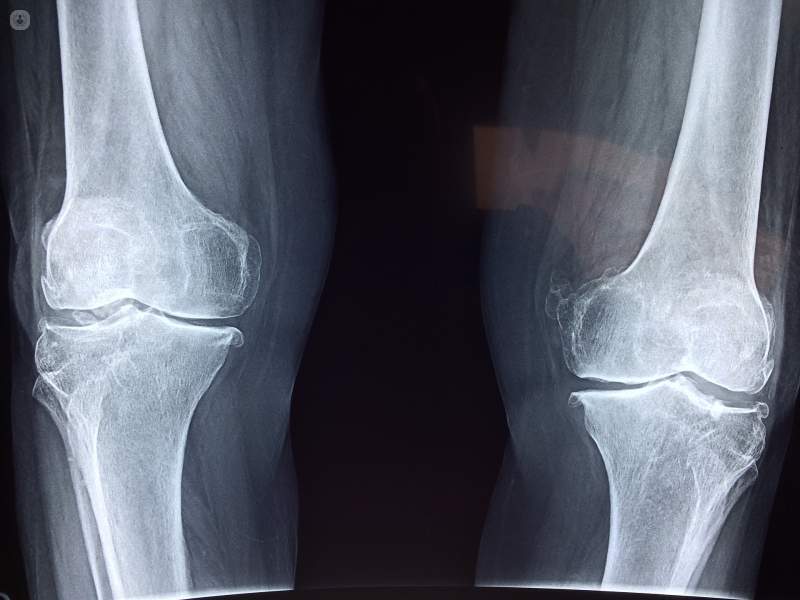

Los tumores óseos benignos son "relativamente frecuentes", según experto

Los tumores óseos benignos son "relativamente frecuentes", sobre todo los que no se consideran agresivos, "y que a veces se descubren casualmente en radiografías realizadas por otro motivo", explica el doctor Javier Carrascoso, jefe asociado del Servicio de Diagnóstico por la Imagen del Hospital Universitario Quirónsalud Madrid, quien advierte que "son lesiones que no hay que tocar y que sólo se deben vigilar".